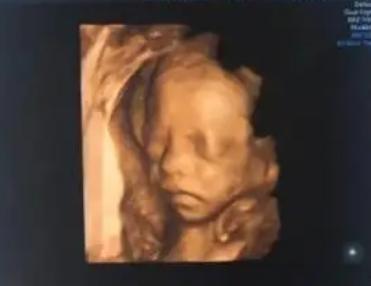

四维彩超检查是一种诊断技术,它可以清晰显示出胎儿的各个发育阶段,因此在确诊孕妇的腹痛、体重下降、情绪波动等情况时,它尤其重要。根据患者的情况,建议进行四维彩超检查。四维彩超检查是一种全面的检查,它可以对胎儿的发育状况进行全面的评估。检查时,医生可以看到胎儿的心跳、血流、活动、脸部表情等,这些信息可以帮助医生判断胎儿的发育情况。此外四维彩超也可以检查胎儿的器官,从而发现胎儿可能存在的畸形或先天疾病。对于孕妇情况较为复杂的情况,建议在第20周进行四维彩超检查。第20周是胎儿发育到一定阶段时,可以更好地了解胎儿的发育情况,也可以更全面、更准确地了解胎儿的器官发育情况。